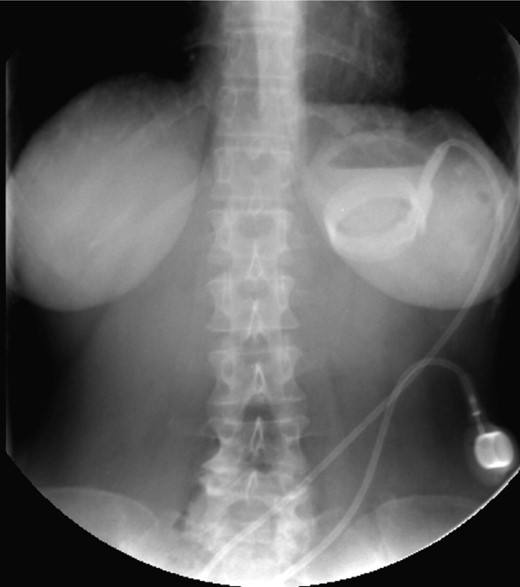

On the first day of admission, gastric banding was completely deflated. Rx abdomen showed posterior slippage of the ring (Fig. 1). Subsequently, the patient underwent rehydration therapy, 20-day total parenteral nutrition and infusion of human albumin. During that period, we examined her upper digestive tract with oral water-soluble contrast (Fig. 2) with the result of a thin liquid passage downstream of the ring and marked gastric pouch distension. Esofagogastroscopy was performed, which was negative for erosion or gastric perforation; however, it revealed a 1-cm-diameter passage through the gastric band. Despite an improvement in symptoms with partial resumption of semi-liquid intake, the patient continued to experience nausea and vomiting. For this reason, she underwent laparoscopic removal of gastric banding. In the operating room, she was placed in the lithotomy position; we placed a 10-mm optical trocar in supraumbilical region, a 5-mm one in the right upper quadrant and a 10-mm one in left upper quadrant near the subcutaneous tank. After lysis of adhesions between liver and stomach, the intraoperative picture showed a banding displacement, confirming posterior slippage of the banding and its sliding back to the level of previous gastro-jejunal anastomosis. Ascitic effusion due to dysproteinemia was reported. A methylene blue test showed no gastric perforation. After this procedure, the patient started to resume liquid intake in the first postoperative day and food intake in the second postoperative day, with complete resolution of vomiting and nausea. Then, she was discharged with the advice of an appropriate diet and invited to attend a recall visit 10 days later. In subsequent follow-up, the complete resolution of clinical symptoms was confirmed together with an improvement of the biohumoral picture.

Water-soluble contrast shows a thin liquid passage downstream of the ring and marked gastric pouch distension.